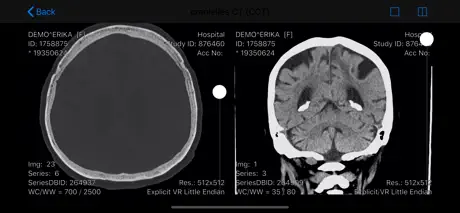

Die RVC Mobile App ist eine native iOS Applikation welche sicher

mit dem einheitlichen RVC Server kommuniziert. Mit dieser App werden iPAD, iPod touch und iPhone zu mobilen Clients die Inhalte aus RVC Clinical PACS / mDMAS intuitiv anzeigen. Dadurch ist ein ortsunabhängiger Zugriff auf das multimediale Archiv möglich. Als Mehrwert dieser Clients wurde auch eine Foto- und Videodokumentation mit integriert, sodass Fotos oder auch Videos direkt vom mobilen Endgerät in das Archiv gespeichert werden können.

- Anzeige von DICOM Objekten

- Vergleichsmodus durch Teilen des Viewports

- Anzeige von DICOM Objekten

Screenshots